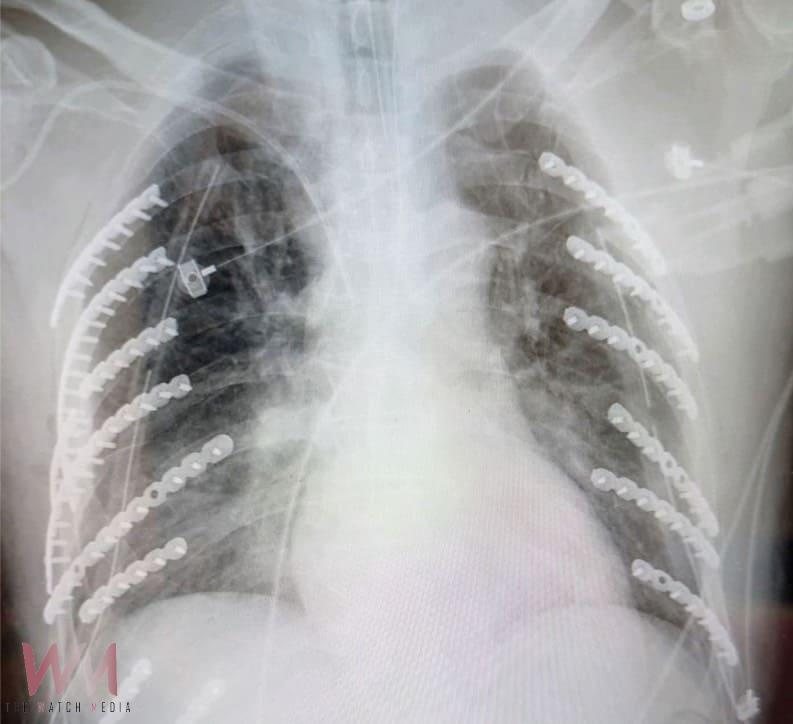

衛生福利部臺中醫院胸腔外科何蕙如醫師表示,患者第一時間被送往最近的急救醫院先插上胸管,確認生命跡象穩定後轉送到院,x光片顯示,雙側同時遭擠壓導致兩側共兩對二十八根肋骨,他就斷了十四根肋骨,甚至一根肋骨斷好幾截,比一般外傷平均斷裂三到五根嚴重許多;另外還合併左側鎖骨及部分脊柱裂傷,以及呼吸衰竭需插氣管內管,病況危急。

幸好斷裂肋骨數量雖多,何蕙如醫師評估肋骨未穿刺血管,在加護病房評估生命跡象穩定後,決定分兩階段手術,第一次植入八根、第二次植入六根鈦合金鋼骨,使肋骨復位固定,術後患者恢復良好,住院三周順利自己走著出院,他還自嘲身上十四根鈦合金,從此變成「鋼鐵人」,跟穿古代金鐘罩一樣厲害。